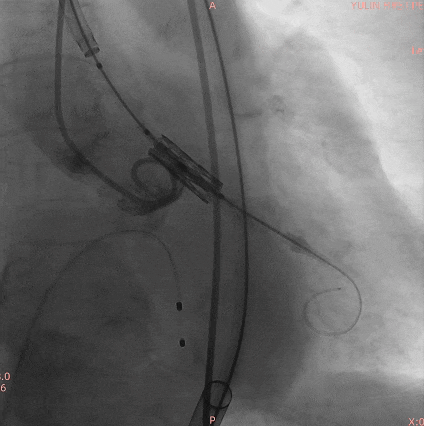

手术过程

通过术前精准评估,患者在全麻下行TAVR手术,DSA和食道超声双重引导,通过穿刺心尖建立工作路径,沿加硬导丝送入19mm*40mm球囊预扩张主动脉瓣,球囊无腰有漏,利用短鞘送入25#RENATUS瓣膜至左室,猪尾巴导管再次造影确认位置。将25#RENATUS瓣膜顺利跨瓣,精准定位,5ATM精确释放,退出输送系统再次行主动脉根部造影,示瓣膜膨胀充分,无瓣口反流,无瓣周漏,冠脉血流正常,术后即刻平均跨瓣压差降至3.62mmHg,超声示术后峰值流速降至0.95m/s。瓣膜释放位置理想、形态及功能良好,瓣叶启闭良好,无外周血管损伤。

术中影像

主动脉根部造影

19mm球囊预扩无腰有漏

25#Renatus瓣膜造影定位

快速起搏下5atm精准球扩释放25#Renatus瓣膜

释放后造影示瓣膜位置理想,形态良好